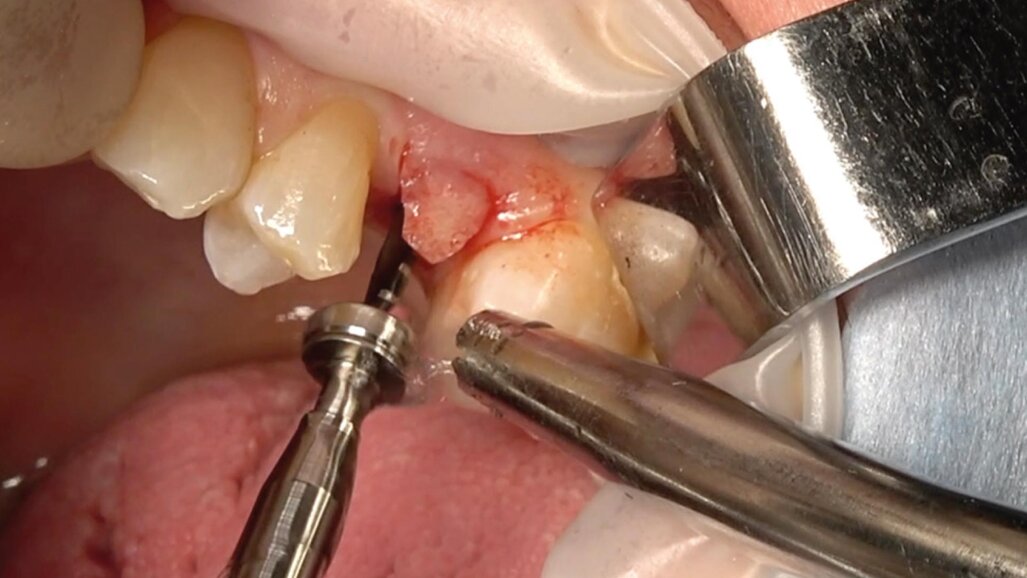

Una paziente di 50 anni presentava un premolare superiore non recuperabile. Dopo CBCT preoperatoria (T0) (Fig. 1), si è proceduto all’estrazione atraumatica e alla gestione dell’alveolo mediante posizionamento vestibolare di una membrana corticale eterologa (Lamina fine 0,7 mm, 35 × 15 mm, OsteoBiol) e riempimento con spugne di collagene (Figg. 2, 3). Sono stati applicati punti di sutura in nylon non riassorbibile 4/0. Dopo sei mesi di guarigione, una nuova CBCT (T1) ha consentito la valutazione della qualità ossea. Per la fase implantare è stato eseguito un lembo secondo la tecnica del roll flap, con preservazione delle papille interdentali e aumento del tessuto cheratinizzato (Fig. 4). È stato inserito un impianto JD Evolution Plus (4,3 × 11,5 mm) ottenendo un’eccellente stabilità primaria. Durante la chirurgia è stato prelevato un campione osseo per analisi istologica (Fig. 5).  Il lembo è stato suturato con nylon 4/0 intorno all’abutment di guarigione. Dopo due mesi, la paziente è stata riabilitata con una corona monolitica in zirconia realizzata da impronta digitale intraorale (Fig. 6).